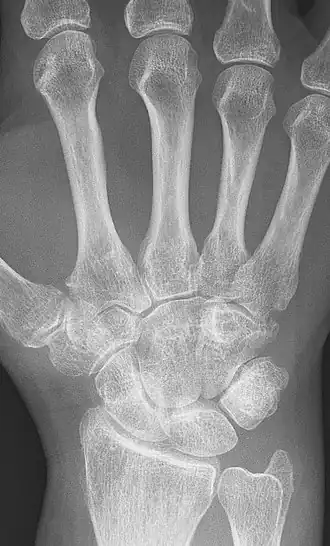

Anquilose dos ossos da mão (carpos) por artrite reumatoide.

Anquilose ou Ancilose (do grego ἀγκύλος, dobrado) é uma adesão anormal com rigidez de uma articulação, resultado de uma lesão ou doença. A rigidez pode ser completa ou parcial e pode ser devida a uma inflamação das estruturas musculares ou tendinosas fora da articulação ou dos tecidos da própria articulação. Em Odontologia é a fixação rígida ou semirrígida que pode ocorrer entre dentes e ossos ou na articulação tempormandibular e é uma das causas da não-substituição de um dente decíduo por um dente permanente.[1]

A sintomatologia clínica (rigidez prolongada e dor em uma articulação) e um raio X que revele fusão óssea é suficiente para esse diagnóstico, mas é importante identificar a causa para decidir o melhor tratamento.